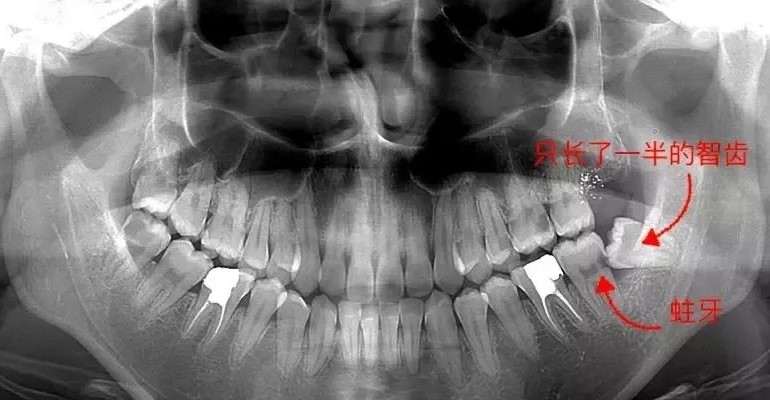

不是所有的智齿都要拔,如果智齿位置端正,则无需拔除。这是因为长歪的智齿不容易清洁,食物常常会留在智齿周围,不仅容易导致智齿疼痛,还容易导致智齿前方的磨牙变为蛀牙,从而引起更大范围上的牙痛。到了那个时候,智齿要拔掉不说,智齿前方的磨牙也会出现不可挽救的龋坏,只能一起拔掉。而且,智齿拔掉之后不需要镶牙,最多花个几百一千块,但如果前方的磨牙被拔掉就只好通过种植牙进行修复。